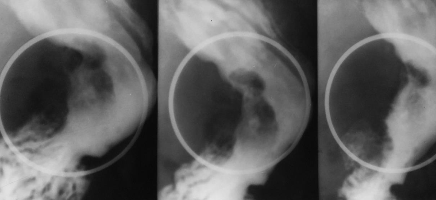

Ulcer gastric

Ulcer piloric